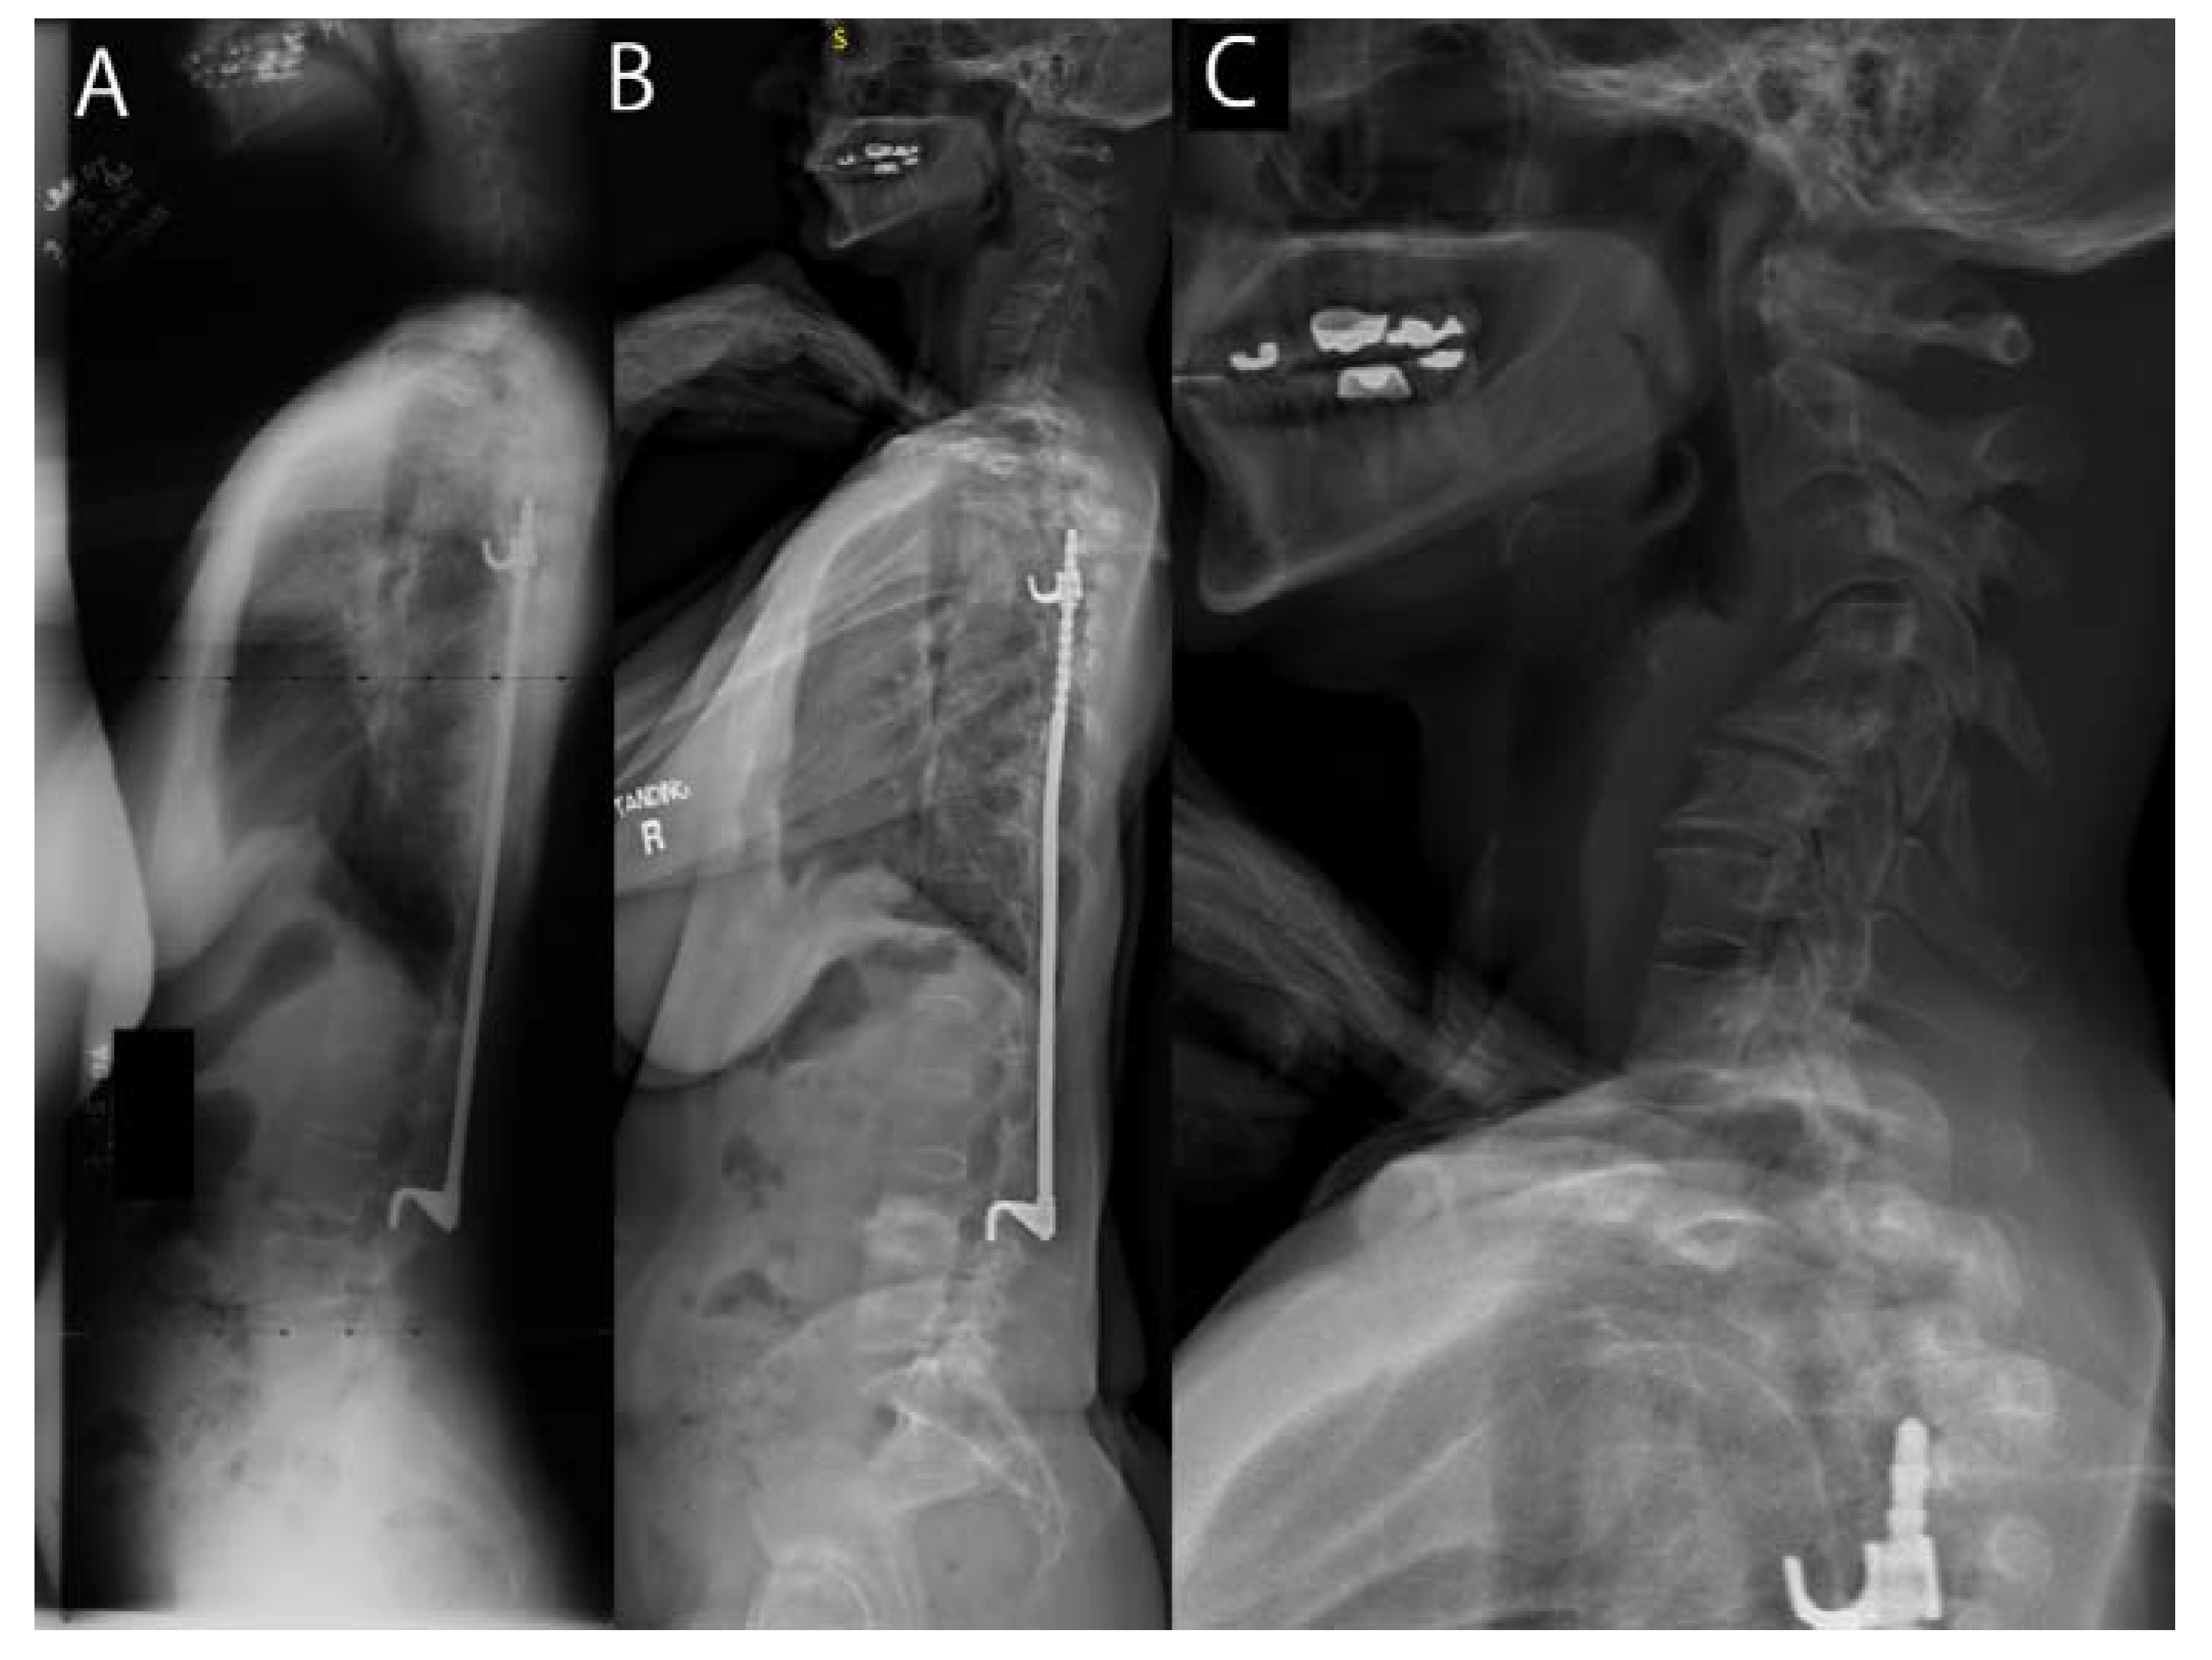

Using Kellgren–Lawrence scoring, we found that 58% of the cohort (19/33) had moderate or severe cervical osteoarthritis (Figure 1). Those with minimal cervical osteoarthritis had a mean age of 40 ± 4.2 years, moderate had a mean age of 39 ± 5.8, and severe cervical osteo arthritis were 50 ± 3.2 years (p < 0.01). There was no difference in the degree of cervical osteoarthritis between the surgical and nonoperative cohorts (Figure 1).

Figure 1.

(A) Child treated with Harrington instrumentation for AIS at age 16. (B,C) Now at 51, she has progressive cervical kyphosis, with severe radicular pain and degenerative cervical arthritis.